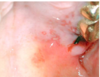

What is this infectious disease?

Describe it

HSV‐1: Primary

Infection

it is a raised blister/papule on the

vermilion

The bottom arrow pointing to a mucosal

ulcer w/ tan pseudomembrane.